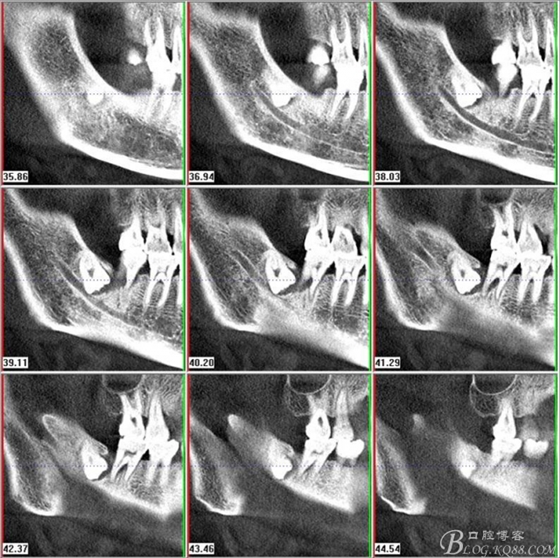

二、術(shù)前CBCT影像:

圖1.47牙冠的近中面緊鄰下頜神經(jīng)管

圖2.判斷47牙根是否吸收

圖3.通過矢狀面和冠狀面來判斷48與下頜管及47的關(guān)系

圖4.水平方向48與47之間的關(guān)系

圖5. 48的三維視圖

圖6.測量48頰、舌側(cè)骨板厚度。

圖7.測量牙冠近遠(yuǎn)中徑的大小及遠(yuǎn)中骨板的厚度